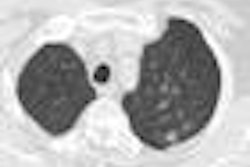

Acting director Horst Hahn will team up with longtime computer-supported medicine researcher Dr. Ron Kikinis in a dual leadership model. Kikinis founded the Surgical Planning Laboratory in 1990 at Harvard Medical School in Boston, and launched the 3D Slicer research platform for analysis and visualization of medical images in the 1990s. He also initiated the National Alliance for Medical Image Computing, a U.S. network of research groups in computer-supported medicine.

The institute said that Kikinis intends to create new synergies by bringing American and European researchers closer together. On the technology side, Kikinis will work on enhancing interoperation between the 3D Slicer software package and the MeVisLab software.